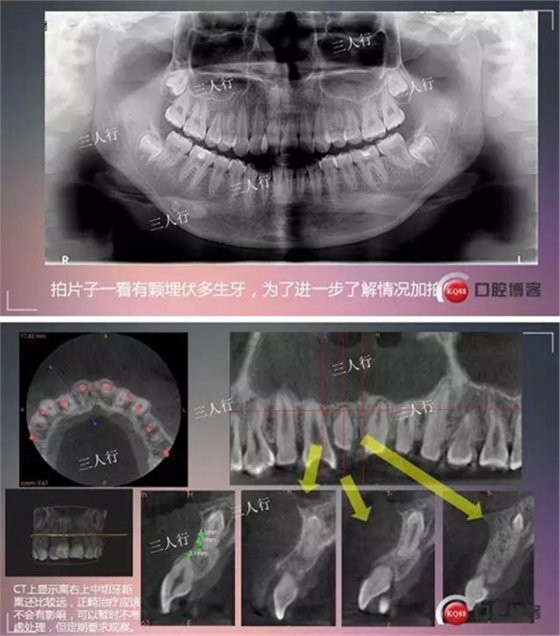

首頁口腔外科 深部埋伏多生牙——微創(chuàng)處理

深部埋伏多生牙——微創(chuàng)處理